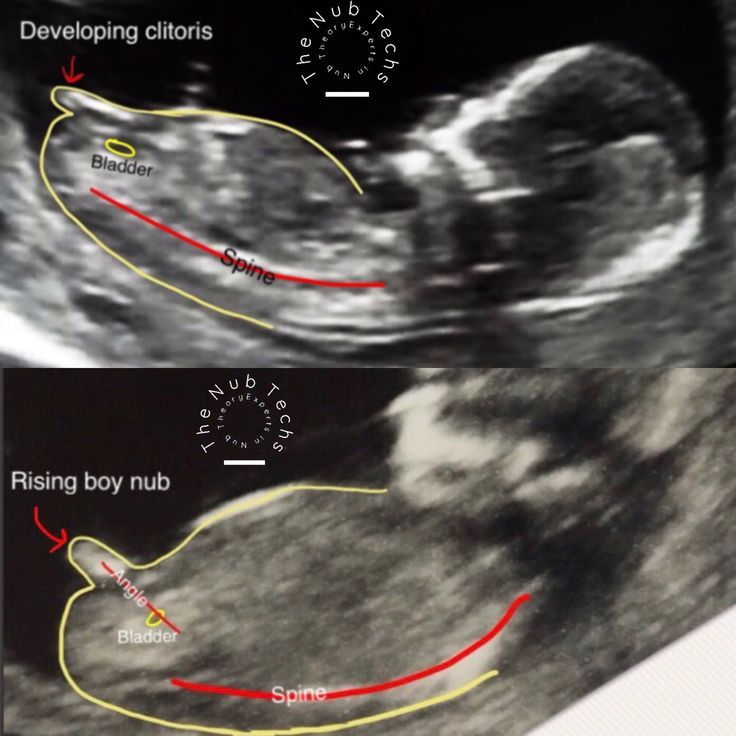

Должно быть вот такого плана фото Изображение На вашем фото неясно...

Ольга , да вроде бы не пуповина)) но мне сказали на таком сроке 13 недель на фото, у всех есть этот бугорок и определяют по углу наклона как-то) спасибо)))

Марьяна, значит если положить малыша на спинку, то этот бугорок смотрит вверх, тогда точно мальчишка)

Марьяна, да, по углу наклона сбоку нужно фото, тут не поймёшь)